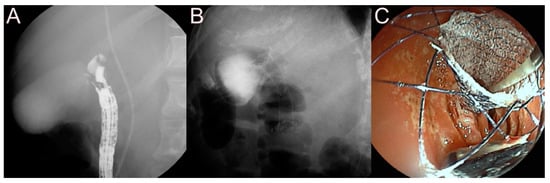

2.4. Stent for EUS-Guided Pancreatic Duct (PD) Drainage

2.4.1. Use of the Plastic Stent

2.4.2. Use of the SEMS